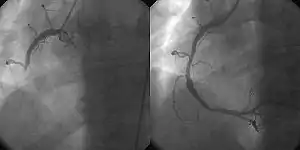

Після госпіталізації лікар обирає стратегію реперфузії, тобто відновлення кровопостачання в ішемізованій ділянці. Це оперативне лікування — черезшкірне коронарне втручання (ангіопластики, встановлення стентів), коронарне шунтування. Фібринолітична терапія (наприклад, альтеплаза, тенектеплаза) показана, якщо оперативне втручання не може бути виконане впродовж 120 хвилин після діагностування інфаркту міокарда з елевацією сегмента ST.